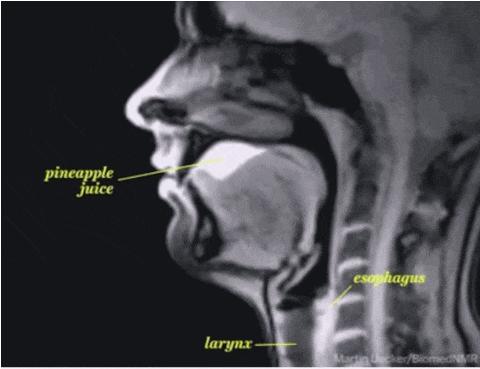

3. 你有沒有好奇過,爲什麼喫東西時食物不會跑錯道?

因爲你的舌根後方,有一塊叫會厭的「蓋子」。

在你吞嚥時,它火速蓋住氣道,防止食物誤入引起窒息;食物嚥下後,它再打開,讓你喘氣。

4. 這是一份精細、繁忙、人命關天的工作,但願會厭不會厭。